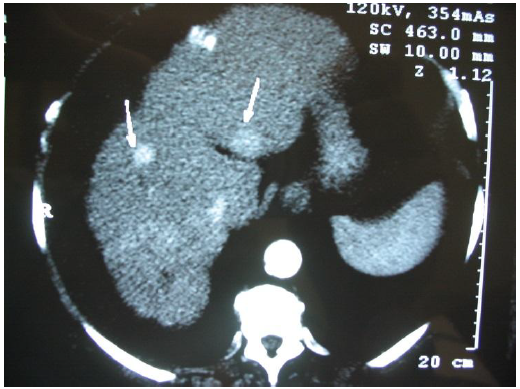

A tomografia computadorizada helicoidal de uma paciente de 56 anos, com hepatopatia crônica causada por vírus C, identificou dois nódulos no parênquima hepático de acordo com imagem abaixo. A paciente apresentava ascite volumosa, encefalopatia GII e icterícia.

A classificação de Child-Pugh é C11.

Assinale a alternativa CORRETA quanto ao tratamento a ser adotado para esta paciente.